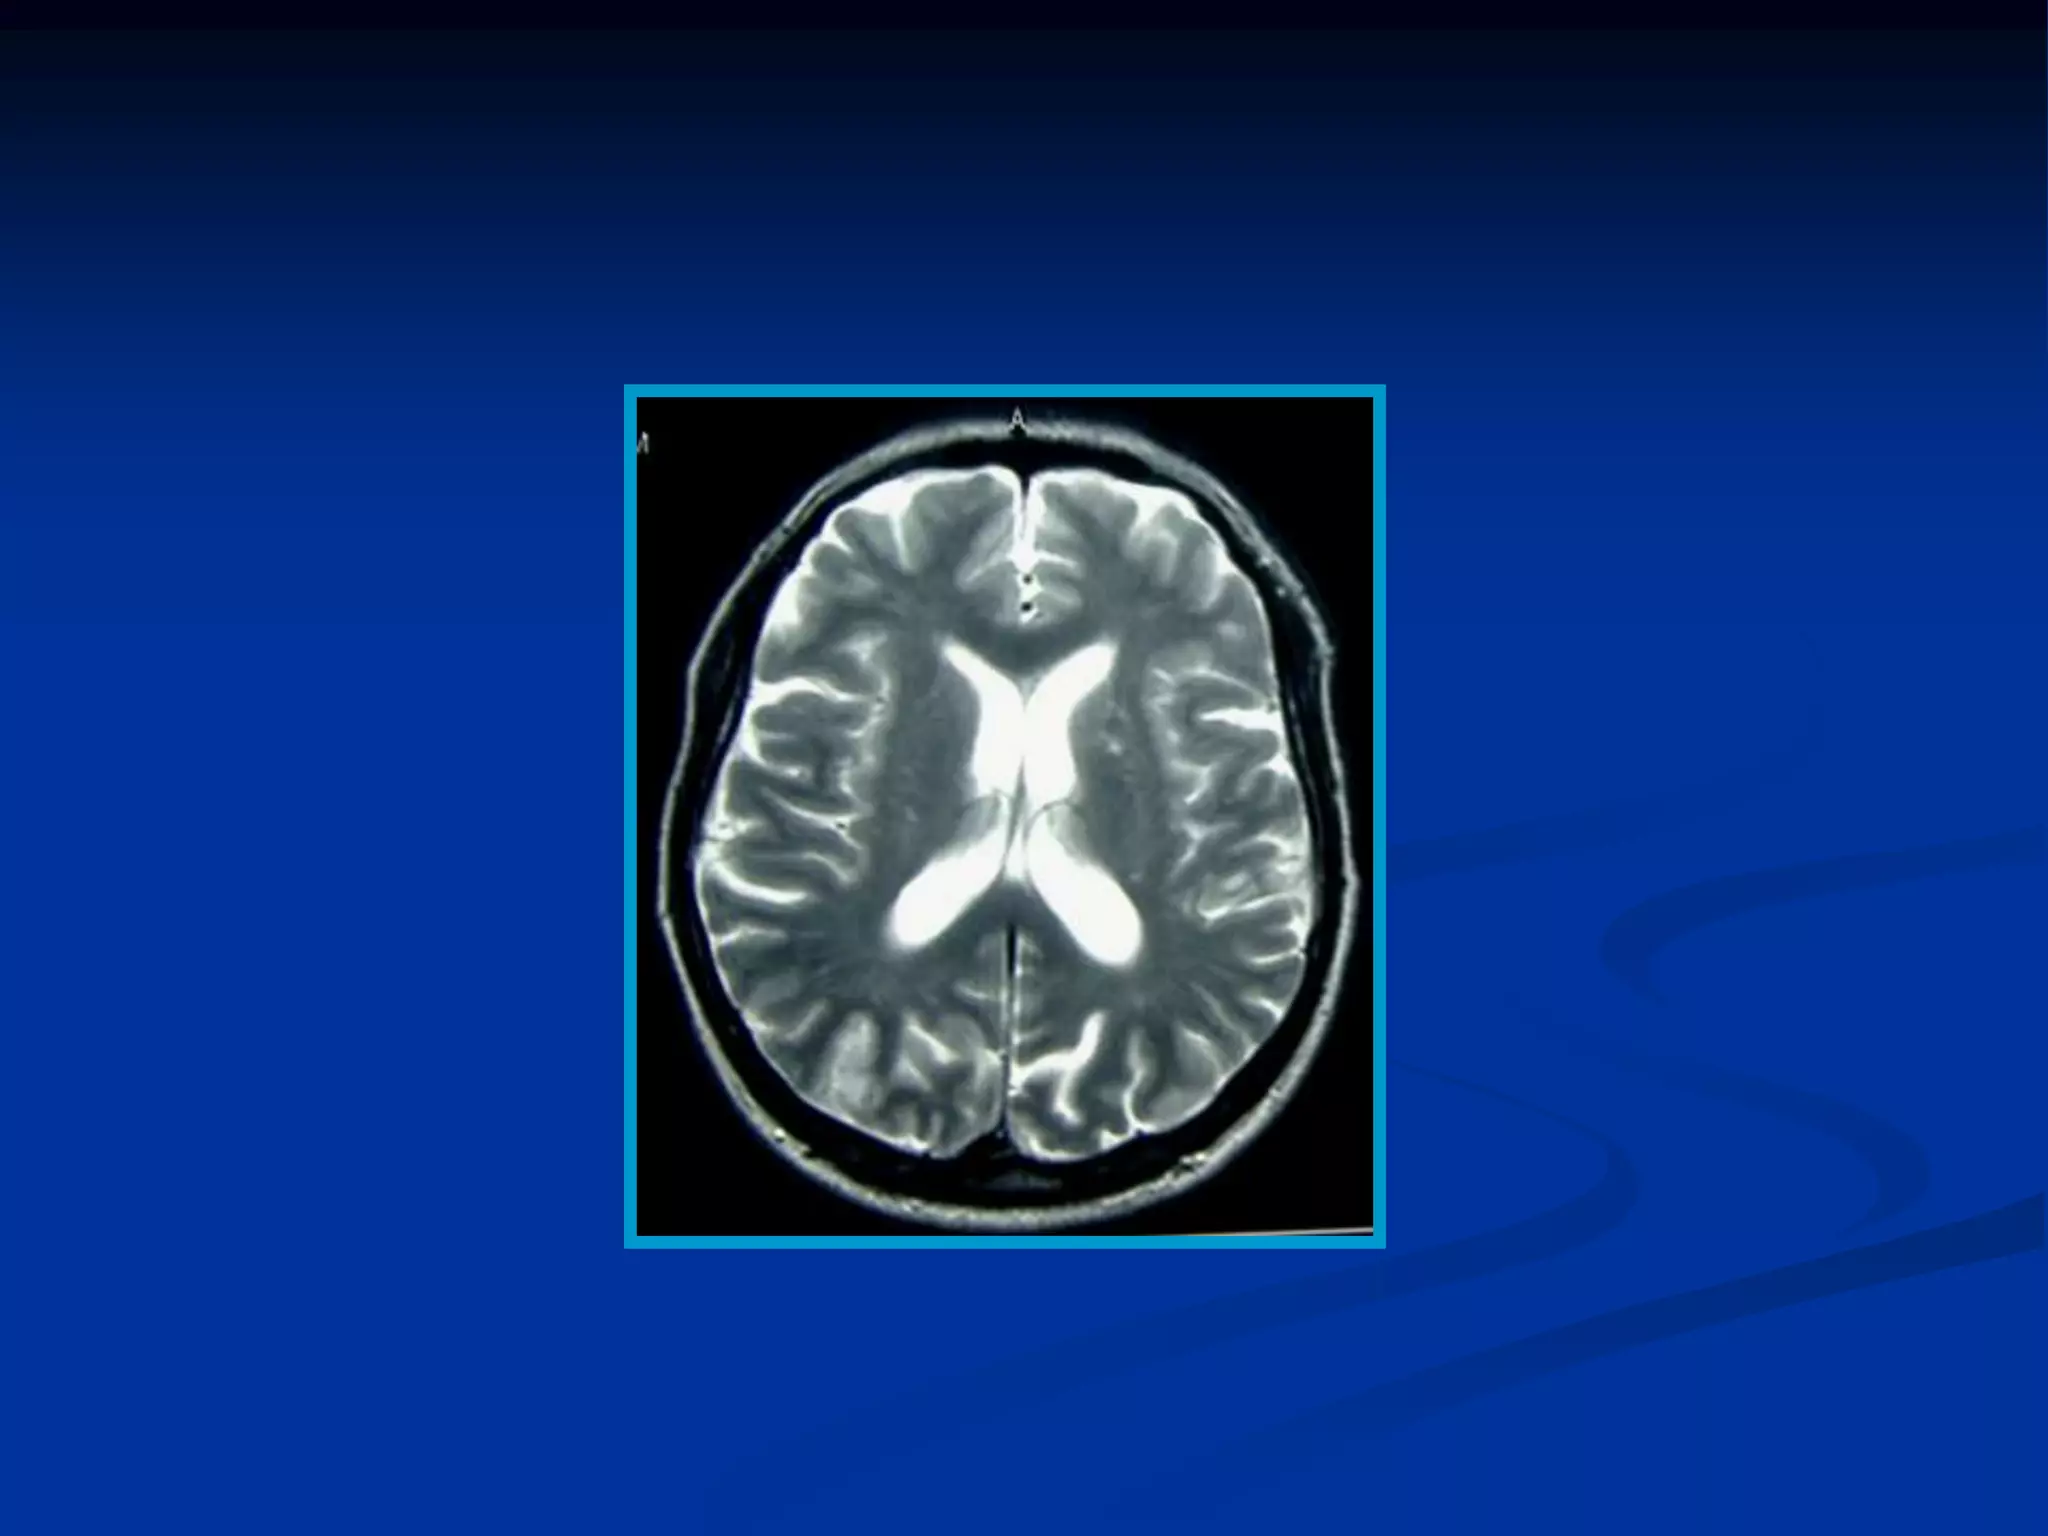

• En el cerebro el LCR, tiene un T1 largo y la señal es

hipointensa.

• La sustancia gris tiene menor intensidad de señal (agua)

que la sustancia blanca (grasa)

Imágenes potenciadas enT1 de los diferentes tejidos según su grado de relajación T1 en un momento determinado • En el cerebro el LCR, tiene un T1 largo y la señal es hipointensa. • La sustancia gris tiene menor intensidad de señal (agua) que la sustancia blanca (grasa)